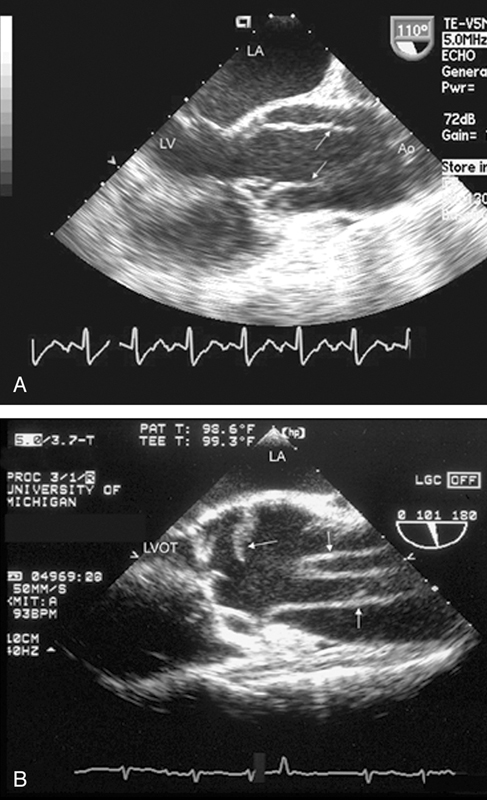

فحوصات تشخيصية لبعض امراض القلب والشرايين التاجية